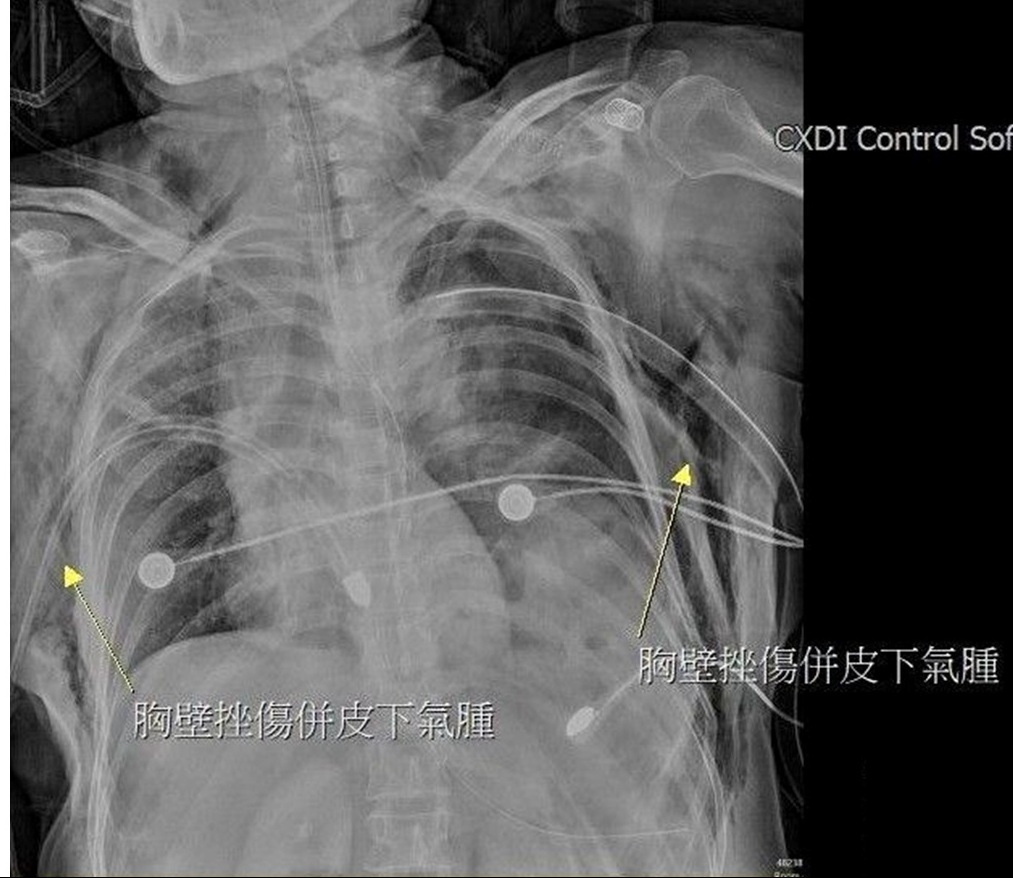

陳姓女子被送抵急診時,出現嚴重的雙側氣胸與皮下氣腫,呼吸極度困難。經全身電腦斷層掃描發現,強大的撞擊力導致她的左側橫隔膜破裂,原本應在腹腔的胃部及部分腸道,竟位移進入左側胸腔,嚴重壓迫左肺,導致肺部無法擴張。此外,檢查更發現其下腹部大量出血(腸繫膜血管破裂)、左腳踝骨折,背部還有大面積的2至3度擦燙傷,傷勢遍布全身。